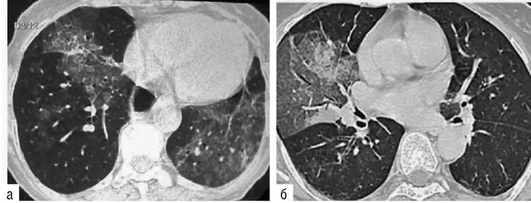

Лучевые методы исследования. Рентгенологическая картина при ЭТА зависит от стадии заболевания. В начальной фазе выявляются признаки отека интерстициальной ткани легких и распространенные мелкоочаговые затенения. При прогрессировании процесса формируются двусторонние изменения легочного рисунка по типу интерстициального фиброза, преимущественно в нижних отделах легких (рис. 2.28). В далеко зашедших случаях определяется мелко- и крупноячеистая деформация легочного рисунка. Описаны случаи, когда единственным рентгенологическим признаком болезни был односторонний плевральный выпот. Отсутствие каких-либо изменений на рентгенограммах отнюдь не исключает ЭТА. Так, при бериллиозе у 23-59% больных может выявляться умеренно выраженная двусторонняя лимфоаденопатия, а в ряде случаев - рентгенотрицательная форма бериллиоза (Dweik R.A., 2015). У 30% из 71 больных ЭТА, наблюдавшихся нами в клинике пульмонологии, в момент обследования изменений на рентгенограммах не было (Орлова Г.П., 2019). Группа больных ЭТА была обозначена условно как рентгенотрицательная группа. Уточнить диагноз помогает КТ легких, выявляющая интерстициальные изменения в легочной ткани по типу «матового стекла», усиление и деформацию легочного и сосудистого рисунка (рис. 2.29), фиброзные изменения тяжистого и звездчатого типов, на поздних стадиях - «сотовое легкое». ВРКТ выявляет «матовое стекло» и другие изменения в легочной паренхиме, которые не видны при обычном рентгенологическом исследовании. Но даже ВРКТ не всегда выявляет изменения в легочной ткани. Так, в 25% случаев гистологически подтвержденного хронического берил-лиоза легких ВРКТ была нормальной (Dweik R.A., 2013; Амосов В.И., Сперанская А.А., 2015; Amanullah S. et al., 2015).

Проведенное нами динамическое исследование КТ-паттернов у 42 больных ЭТА показало трансформацию отдельных типов интерстициальных пневмоний по мере прогрессирования патологического процесса в фиброзную НСИП или ОИП (рис. 2.30), что подтверждает объединительную концепцию интерстициальных пневмоний вне зависимости от этиологического фактора, которые являются не отдельными нозологическими формами, а стадиями течения фиброзирующего процесса в легких (Илькович М.М., Новикова Л.Н., 2018; Орлова Г.П. и др., 2019).

Исследование легочно-сердечной гемодинамики. При эходоплеркардиографии отмечается увеличение систолического давления в легочной артерии за счет повышения общего легочного сопротивления по отношению к нормальным величинам. Наличие нарушений гемодинамики малого круга кровообращения подтверждается данными сцинтиграфии легких с 99m[Tc], указывающими на диффузные нарушения перфузии разной степени выраженности. Перфузионная сцинтиграфия позволяет выявить осложнение альвеолита тромбоэмболией мелких ветвей легочной артерии. Так, при амиодарониндуцированном ЭТА в 31,1% случаев могут выявляться субплевральные участки консолидации легочной ткани, подозрительные на присоединение тромбэмболии мелких ветвей легочной артерии (Яковлева Н.С. и др., 2019). В этих случаях диагностика тромбоэмболии по данным КТ затруднена на фоне текущего альвеолита или распространенных фиброзных изменений. По нашим данным, из 16,7% больных только у 3,3% ТЭЛА была выявлена при ангиоКТ, а у 13,4% больных признаки тромбоэмболии мелких ветвей легочной артерии выявлялись при перфузионной сцинтиграфии с Тс-99-МАА (рис. 2.31).